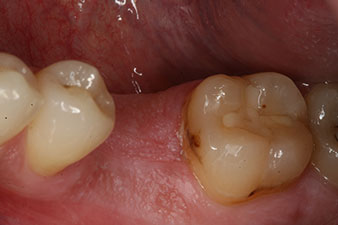

measuring probe

Fig. 6: Ten weeks later the gingiva former, which was screwed in place after placement of the implant, can be removed. In the linguo-buccal direction the ISQ value was virtually unchanged at 63 (measuring probe in proximity at a distance of 2-3 mm).

The implant was uncovered two months later and a gingiva former was screwed in (no picture).

After healing of the soft tissue, the implant stability was measured again before delivery of the prosthetic restoration.

Both values were virtually unchanged and were between the medium and the high range – where the lower value is always used as the reference value that determines the treatment.